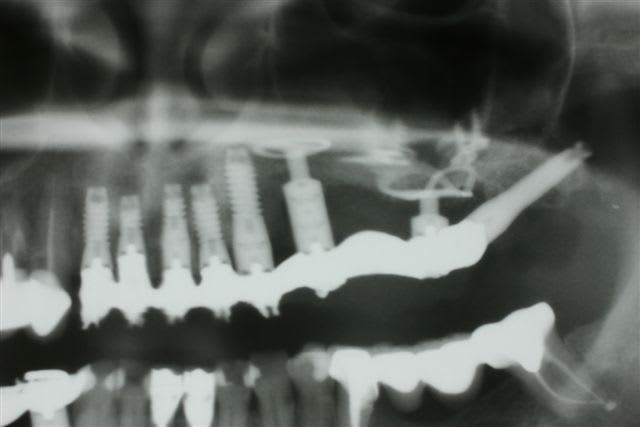

1 Radiographie panoramique avant implantation.

Les deux implants du haut ont été perdus.

2La greffe autologue prélevée à la hanche à totalement fondu.

Il ne reste que la vis d'ostéosynthèse qui avait servi à fixer le greffon.

3 Radiographie Panoramique de la correction

4 Utilisation d'un implant à plaque.

La vis d'ostéosyntèse impossible à dévisser a dû être coupée.

5 Un bridge transitoire a été mis en place deux jours après la pose des implants

et roule mais pour la pérennité du cas une équilibration due l'ensemble de la bouche .....